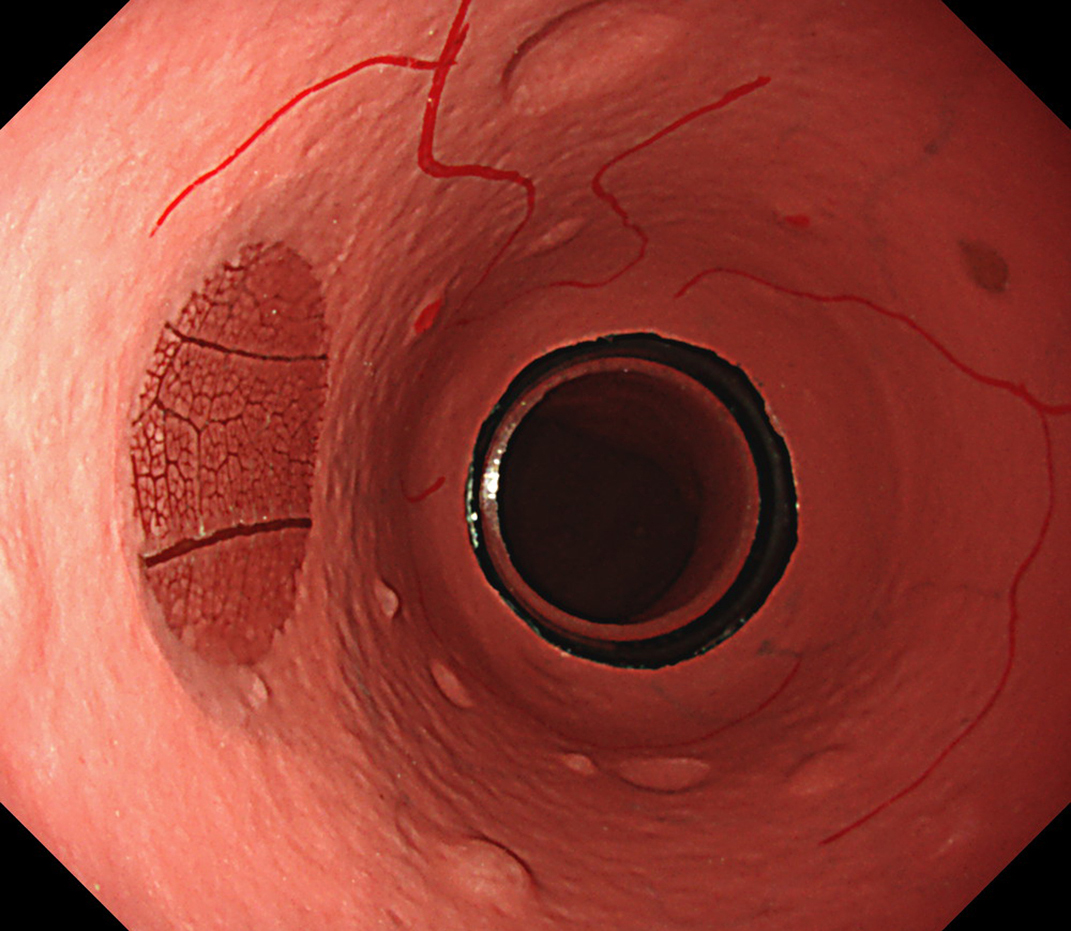

EVIS LUCERA ELITE × GIF-1200N 、EVIS X1 × GIF-H190N 什器比較画像

面順次式、同時式で色味の違いはありますが、どちらもハイビジョン画質にて観察可能です。

EVIS X1×GIF-H190N